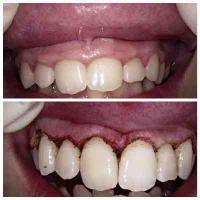

Laser Gum Contouring / Gummy Smile Correction

Laser Gum Contouring Procedure

In the past, patients who were troubled with "gummy" smiles could have the prominence of their gums reduced with a scalpel, which could cause bleeding and an uncomfortable recovery. Now, with the advent of laser dentistry technology, and tools such as the diode laser, patients can have their gums sculpted to perfectly accent their smiles in a fast, simple, and virtually painless procedure.

To begin the laser gum recontouring process, your mouth is numbed with a local anesthetic to eliminate any discomfort. We will then use a diode laser to gently cut away excess gum tissue and sculpt a more uniform, scalloped gum line. Diode lasers cauterize while they cut, which means less bleeding and a dramatically reduced chance of infection for patients. The entire gum lifting procedure can be completed in just one brief visit to our office.